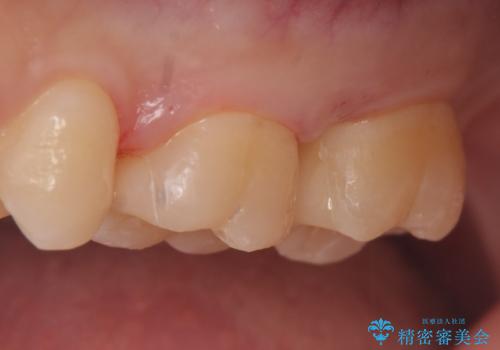

術後歯肉の回復を待ち、左下6、7ともにセラミックインレーによる修復を行いました。

当院のセラミックインレーはemaxという強度と審美性に優れた材料を使用しています。

またプレス方式でインレーを製作しているため、削り出しで製作するCADCAMより優れた適合性も持ち合わせており、虫歯が再発しにくい修復物です。